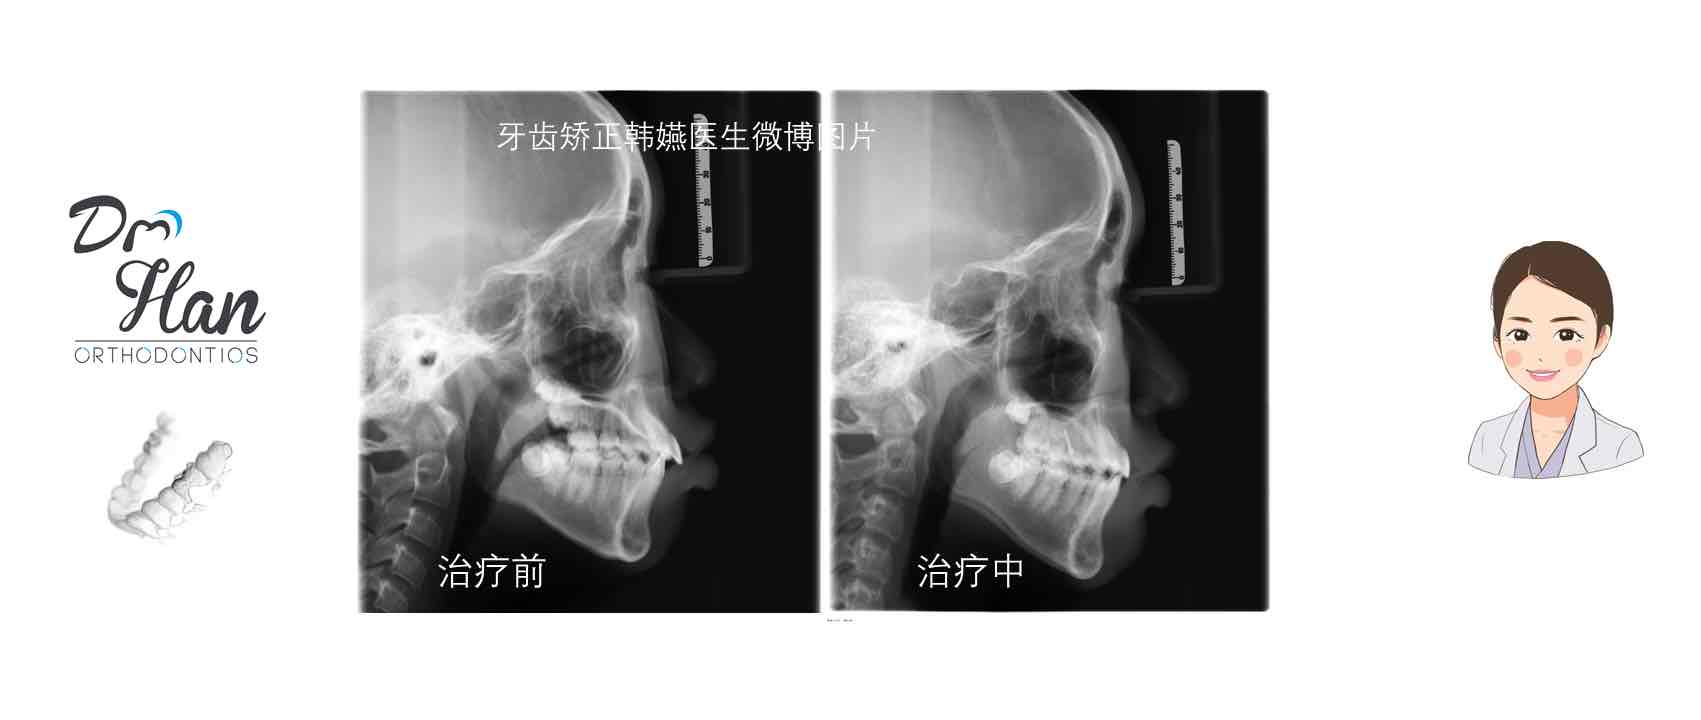

#隐适美拔牙矫正病例# 嘟嘟嘴变身小鲜肉咯[呲牙]